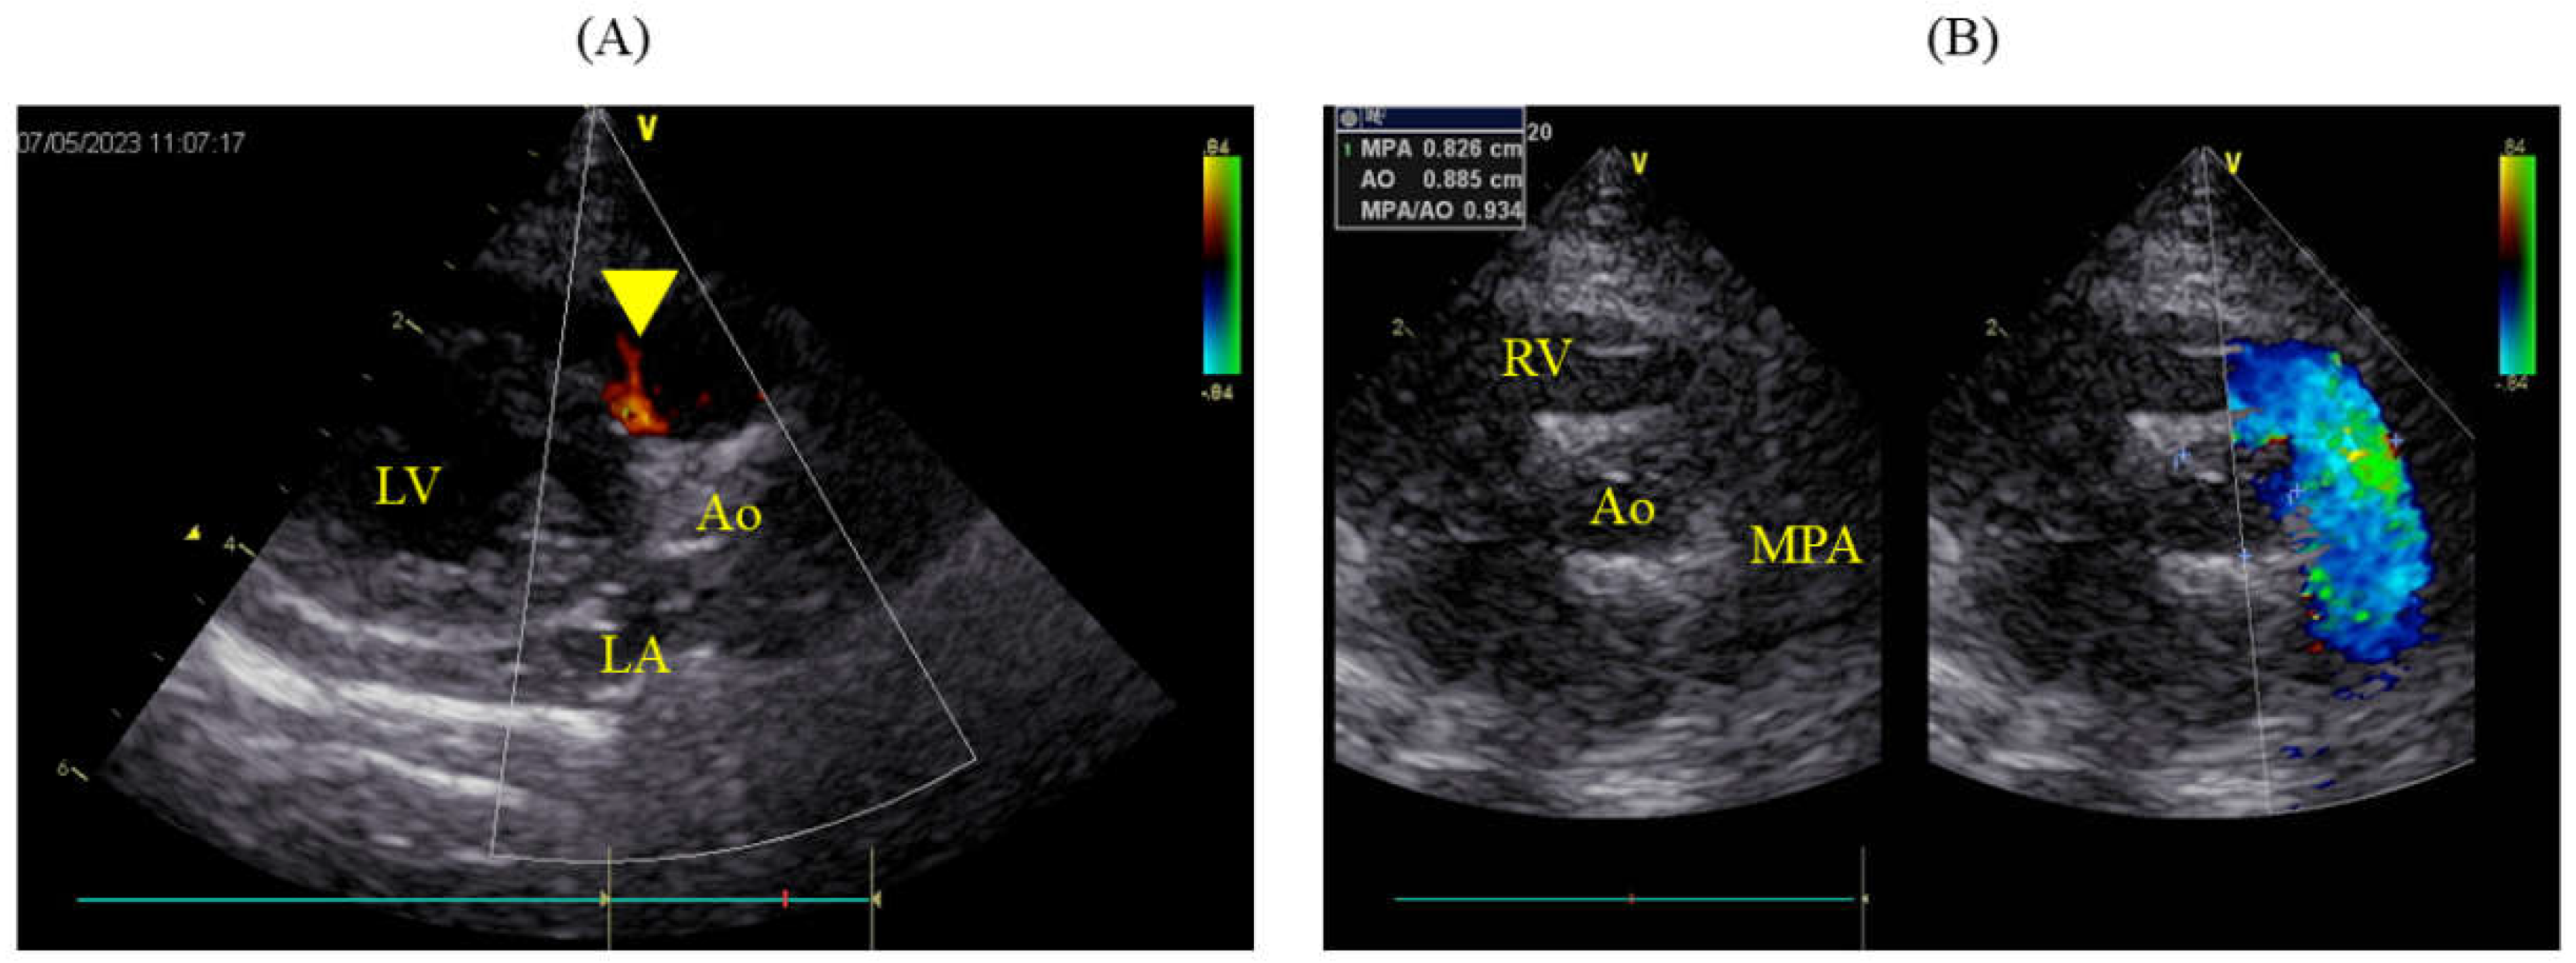

The packed cell volume (PCV) decreased to 15.7% postoperatively, necessitating a transfusion of 49 ml of blood, after which the PCV on the following day was 24.3%. Urine output immediately post-surgery was maintained at 2 ml/kg/hr but subsequently decreased, and by the second postoperative day, azotemia was observed (blood urea nitrogen, BUN: 78.5 mg/dL; creatinine, Cre: 3.6 mg/dL). Blood potassium level remained normal at 4.03 mmol/L. Continuous fluid therapy resulted in normalization by postoperative day 12 (BUN: 26.0 mg/dL; Cre: 1.2 mg/dL). However, by postoperative day 7, the pleural effusion had turned milky, requiring approximately 100 ml/day to be drained. The triglyceride (TG) and total cholesterol (T-Chol) levels in the pleural fluid were 60.0 mg/dL, with serum levels at TG 59.0 mg/dL and T-Chol 183.0 mg/dL. From postoperative day 8, oral administration of rutin 500 mg three times daily was initiated. A contrast-enhanced CT scan under anesthesia was performed on the postoperative day 12. The thoracic duct was highlighted using an iodinated contrast (iohexol 300 mg/ml; Fuji Pharma Co., Ltd., Tokyo, Japan) injected subcutaneously at 1.8 ml/kg around the anus, followed by 5 min of massage. This revealed significant collateral development in the anterior chest and leakage of the contrast agent into the pleural cavity. No thrombi or embolic material was found in the cranial vena cava. The milky effusion gradually decreased and resolved by postoperative day 15, allowing removal of the chest drain on the following day and discharge on postoperative day 17. Antithrombotic therapy was not implemented in this case. On the postoperative day 490, the patient remained asymptomatic and lively, with no recurrence of the chylothorax. Echocardiography showed slight residual shunting from the VSD (Figure 4A), but the pulmonary artery had returned to normal (MPA: Ao 0.93; 8.3/8.9 mm), and both LA/Ao and LVIDd were within normal ranges at 1.41 (1.25/0.89 cm) and 1.18 cm, respectively (Figure 4B).

Figure 4. Echocardiographic findings 490 days post-operation. (A) Right parasternal long-axis view of the LV outflow tract, where color flow Doppler is slightly adjusted to confirm residual shunting, showing minor residual shunting (yellow arrow-head). (B) Simultaneous right parasternal short-axis view at the level of the aortic valve indicating the diameters of the aorta at 8.9 mm and MPA at 8.3 mm, with an MPA:Ao ratio of 0.93. LA: left atrium; LV: left ventricle; Ao: aorta; MPA: main pulmonary artery; RV: right ventricle.